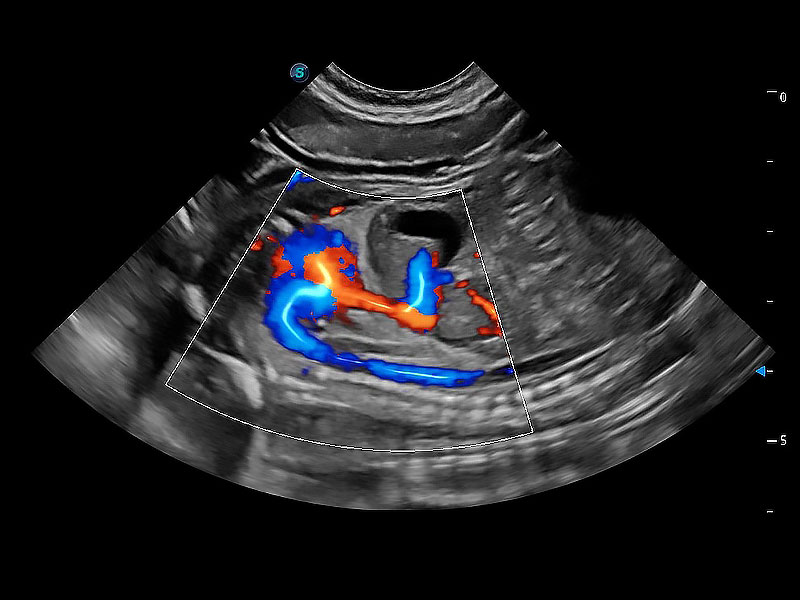

(犬)胎儿主动脉弓立体血流